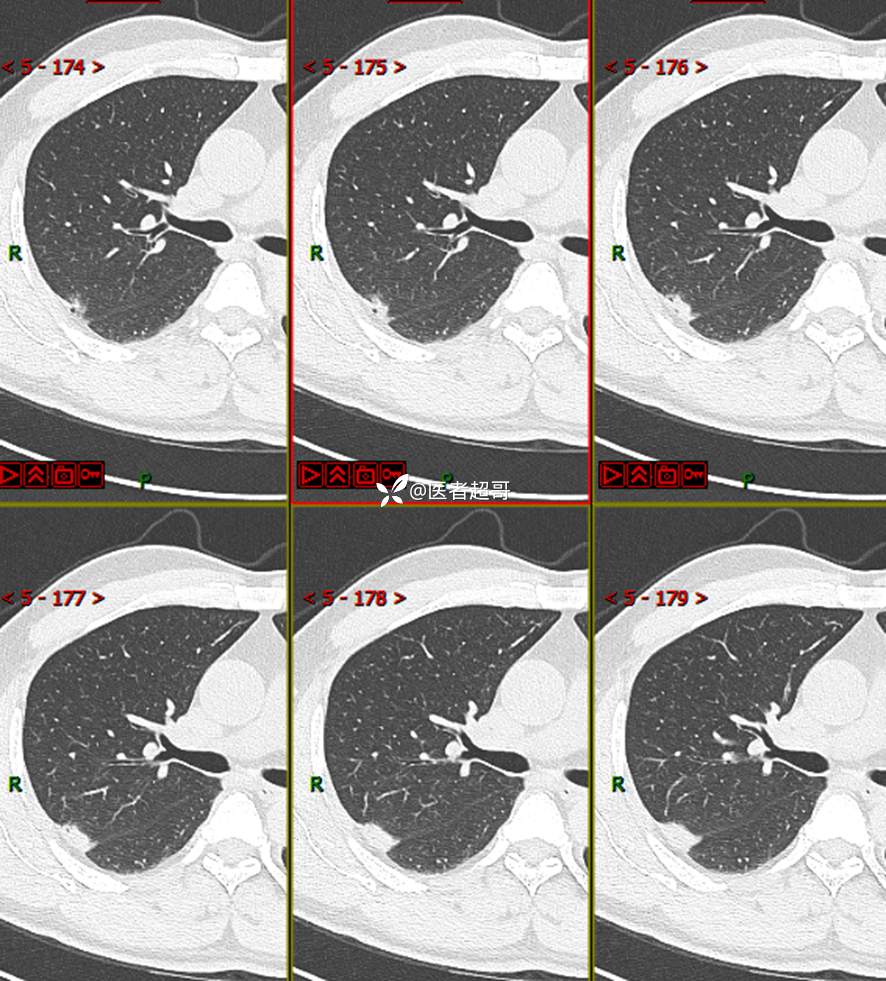

现病史:患者1年余前于体健中心行胸部X片发现右上肺叶密度增高影,无明显咳嗽,咳痰,无痰中带血及咯血,无胸痛及胸闷、气短,无发热、盗汗及全身乏力。无头痛、头晕,无腹痛、腹胀及恶心、呕吐,无声音嘶哑及呛咳,未行特殊治疗。后患者定期复查胸部CT,未见明显变化。2023-2-6患者于我院复查胸部CT:右肺上叶、下叶交接处胸膜下见实性结节影,最大截面约2.6cm×1.4cm,较前增大,建议行手术治疗。今为求进一步诊治,遂来我院就诊,门诊以“肺肿物”收入我院,患者自发病以来,神志清,精神可,饮食可,睡眠良好,大小便正常,近期体重未见明显增减。